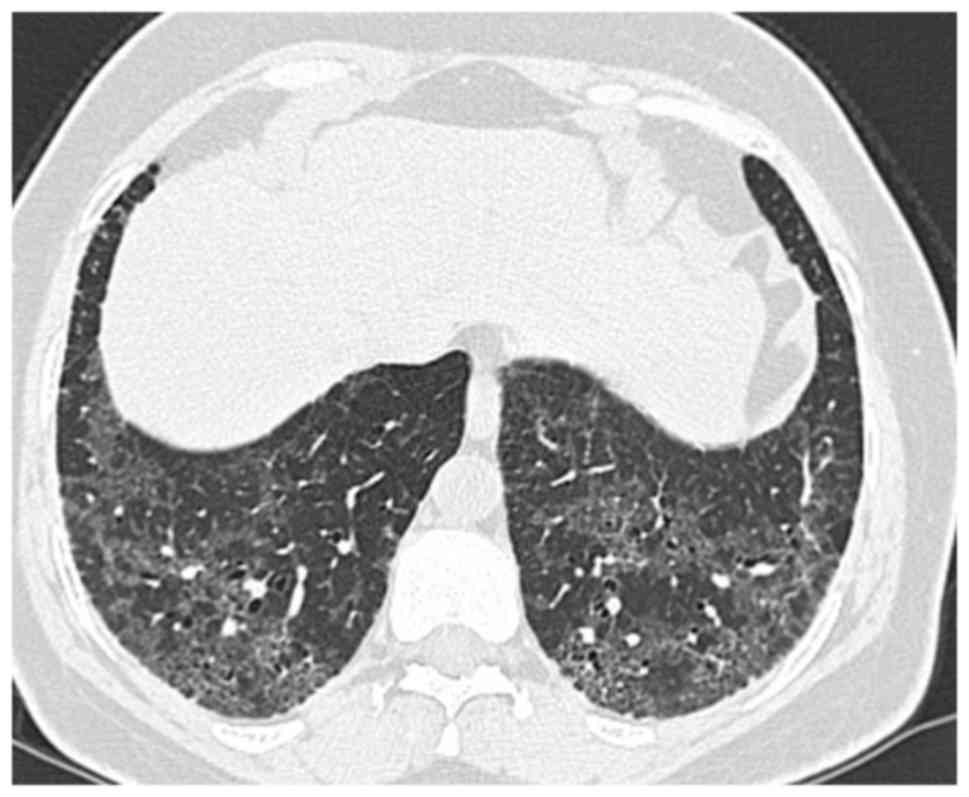

Diagnostic radiological findings are rather apparent from thoracic high-resolution computed tomography (HRCT; Fig. 2; patient provided informed consent for inclusion in the present study). An invariable HRCT finding is the presence of a diffuse ground-glass appearance, usually symmetrical and frequently involving the middle and lower zones (6,36,37). While involvement of upper zones is seen in most cases, their predominant involvement is relatively rare. All regions may be affected, although subpleural involvement is most common. Other HRCT findings include irregular lines and traction bronchiectases indicating parenchymal distortion (38). Peripheral microcysts implying dilated bronchioles and alveolar ducts may be seen (39). Honeycomb appearance is not common.

Figure 2.

Disorganized ground glass opacity, interlobular septal thickness and minimal honeycomb-like structures were seen on high-resolution computed tomography of the thorax. This is the same patient as presented in Fig. 1.